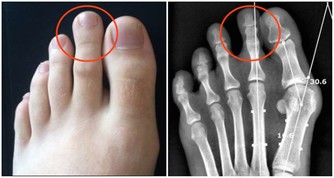

6.潛在病因:除了疼痛,還要警惕可能導致猝死的潛在病因。

比如,是否有易形成血栓的病史。

例如一位骨折病人,他 曾在一段時期內被限制運動,那麼他就容易發生靜脈血栓,

而靜脈血栓一旦掉下來,則可能發生肺梗死。